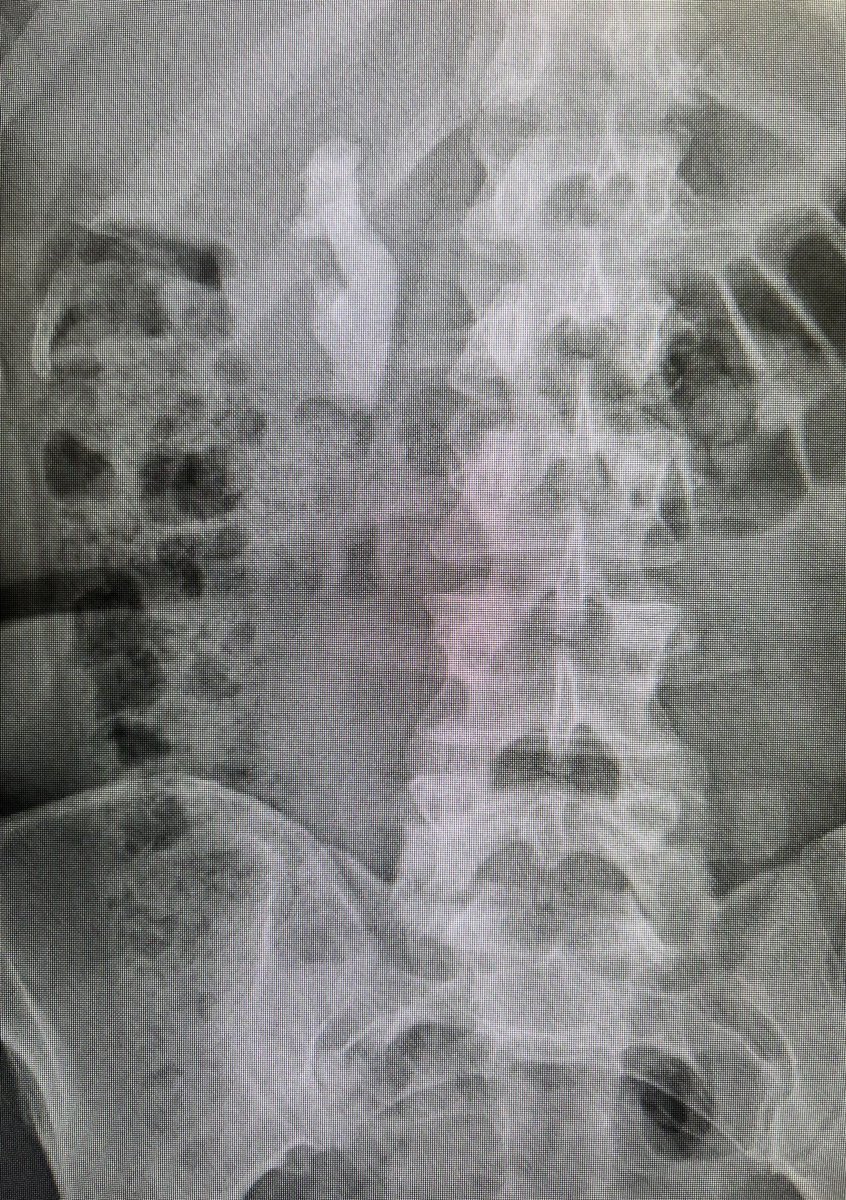

Supine #Superminiperc, 14Fr with suction & flexy ureteroscope ( MiniEcirs). It works perfect even for Staghorn @emiliani_e @koey_kana @JorgeMiguelRob @pizquierdog . Thanks Prof @zeng_guohua